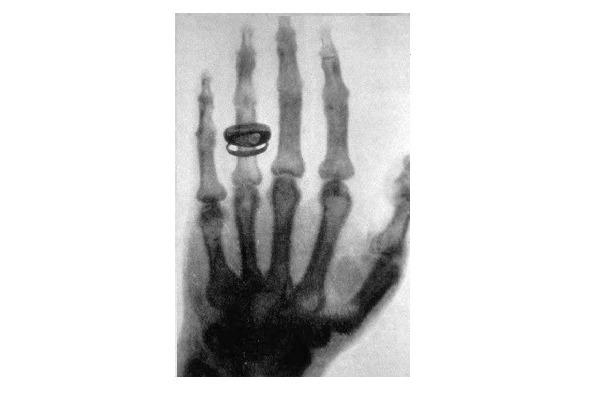

Главное открытие в своей жизни Конрад Рентген сделал 8 ноября 1895 года. Работая в своей лаборатории, он заметил, что после включения тока в катодной трубке начинает светиться покрытый слоем платиноцианистого бария бумажный экран. Это происходило вопреки здравому смыслу, поскольку трубка была полностью закрыта плотным черным картоном, и свет не мог проходить через него. Когда рентген выключил ток, свечение прекратилось, а при включении тока экран снова засветился! Он сделал вывод, что в трубке возникают икс-лучи, способные проходить через плотный материал

Рисунок 2. Первый рентгеновский снимок — рука Альберта фон Келликера, 21.01.1896 года

и вызывать флуоресценцию определенных веществ. В зависимости от вида материала и его толщины преграда пропускала больше или меньше луче, что позволяло анализировать структуру различных объектов. Установка, разработанная Рентгеном, выполняла совершенно новую функцию — неразрушающий анализ структуры непрозрачного объекта.

— Рентгеновский аппарат не мог бы быть создан без открытия Рентгеном икс-лучей (за которое он, кстати, получил Нобелевскую премию по физике за 1901 год и право на дворянский титул!).